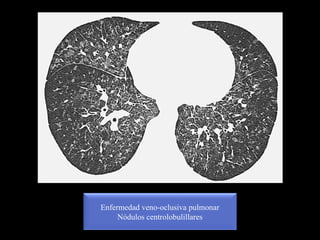

Enfermedad veno-oclusiva pulmonar

Nódulos centrolobulillares